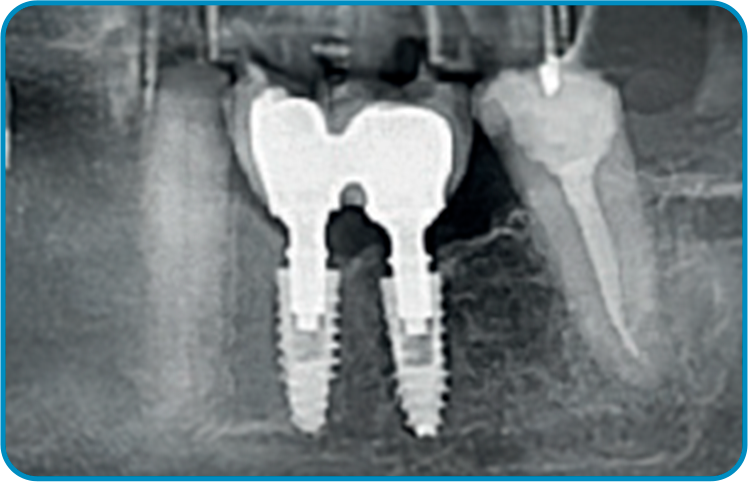

O caso clínico iniciou-se em 2015 com o objetivo de restaurar função e estética. Foram instalados dois implantes nas regiões dos dentes 35 e 36, seguidos pela osseointegração e condicionamento tecidual. As próteses finais foram confeccionadas sobre pilares Arcsys, com ajustes oclusais precisos. O acompanhamento clínico completa dez anos, com exames periódicos e manutenção regular. Observa-se excelente estabilidade óssea e saúde peri-implantar. O caso comprova que protocolos bem executados e componentes de qualidade garantem longevidade previsível.

2 | Imagem radiográfica após a instalação dos implantes e componentes protéticos.

3 | Exame de imagem realizado 120 dias de pós-operatório, após instalação da prótese.

4 | Acompanhamento radiográfico de dois anos em função.

5 | Imagem radiográfica evidenciando a estabilidade tecidual ao redor dos implantes após dez anos de função.